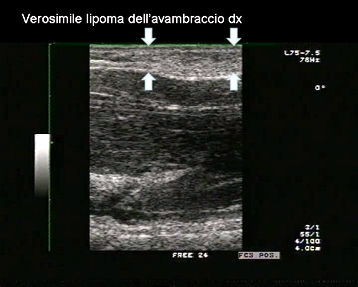

Età paziente: M 12 anni

Motivazione dell'esame: tumefazione dura, non dolente all'avambraccio destro, riscontrata da alcune settimane.